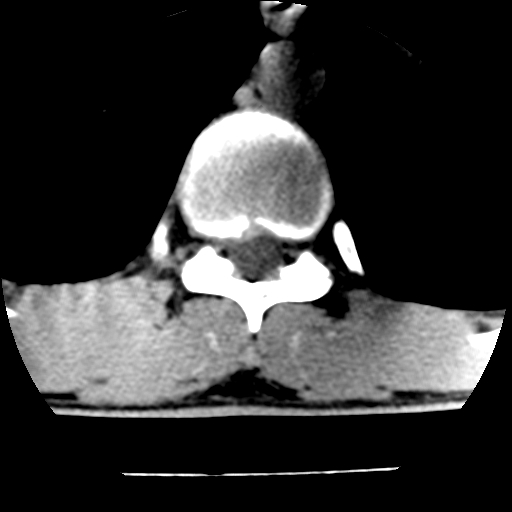

男,31岁,从6米高处坠落伤两天,腰背部疼痛,临床要求ct扫描胸10-腰1。请大家帮忙看看骨质有问题吗?

t12、l1锥体前缘轻度楔形变,平扫示椎体前缘骨小梁欠规整,第9幅图示椎体前缘骨质不连续,结合外伤史考虑椎体轻度压缩骨折。

楼主扫描层厚可能较大,每个椎体只有三个层面.

从所示层面分析,无明确骨折征象,象类似病人我个人会建议mri除外骨挫伤.

从上查骨窗第九片椎体前缘皮质显示断裂.压缩骨折?